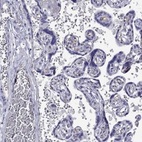

Immunohistochemical staining of human placenta shows moderate membranous positivity in endothelial cells.